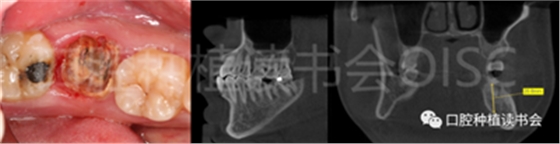

C型拔牙窩,幾乎沒有間隔骨,因此需要種植體與拔牙窩周邊貼合。一般而言,種植體應(yīng)超過(guò)根尖至少 3-5 mm,以獲得初期穩(wěn)定性(圖8、圖9),但在后牙位點(diǎn),這樣比較困難;最常見的原因是下牙槽神經(jīng)或上頜竇靠近根尖。

圖8 上頜殘冠根方與上頜竇底之間有充足的骨,可用于獲得種植體初期穩(wěn)定性。

圖9 完成種植體即刻植入,利于根方骨獲得足夠的初期穩(wěn)定性。

在不存在牙槽間隔骨的 C 型牙槽中,常規(guī)種植體可能很難獲得初期穩(wěn)定性。因此,為了在大多數(shù) C 型拔牙窩中獲得植入物穩(wěn)定性,需要非常寬的種植體。此外,擁有較厚的頰舌側(cè)骨壁,拔牙和種植體植入后的牙槽嵴結(jié)構(gòu)發(fā)生顯著變化的可能性降低。如果 C 型拔牙窩部分或全部頰側(cè)壁缺失,則不應(yīng)植入種植體。